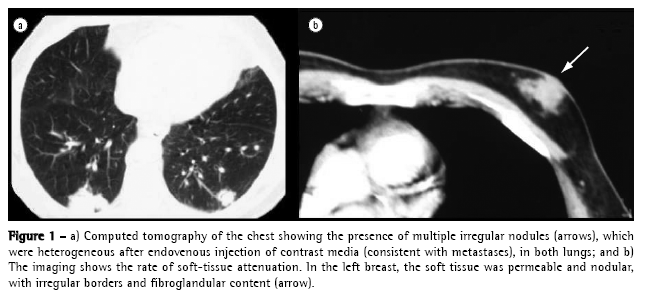

Chest X-rays showed multiple nodules in both pulmonary fields consistent with metastases, which were confirmed through tomographic study. In addition to the pulmonary metastases, there was an accidental X-ray finding of a mass consistent with neoplasia in the left breast (Figure 1).

A puncture biopsy of the lesion was carried out, and a diagnosis of invasive ductal breast carcinoma was made. The patient claimed to have no family history of breast cancer and refused to be submitted to any type of treatment.